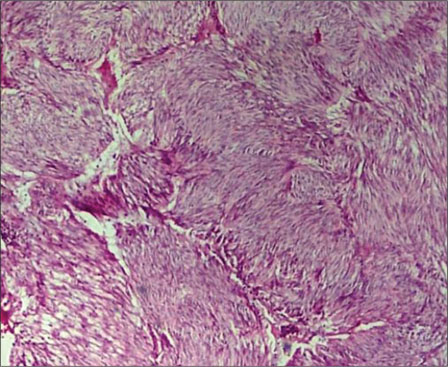

A total of 90 mesenchymal tumors of the GIT and pancreas diagnosed in SKIMS from January 2010 to December 2016 were reclassified on the basis of morphologic features and IHC into 77 (85.6%) cases of GIST and the remaining 13 (14.4%) cases as other mesenchymal tumors. The mesenchymal tumors included five cases of inflammatory myofibroblastic tumors, two cases of leiomyoma, four cases were sarcomas, one case was poorly differentiated carcinoma, and one was desmoid tumor. C-KIT positivity was seen in 72 (93.5%) cases and DOG 1 was positive in 77 (100%) cases [Figures 1], [2], [3], [4]. However, the correlation between DOG1 and CKIT was found to be statistically insignificant (P = 0.23). There was no significant association between DOG 1 expression and various histopathological parameters in the studied cases. Clinicopathological variables have been enumerated in [Table 1].

| Figure 2 Microscopic view of gastrointestinal stromal tumor